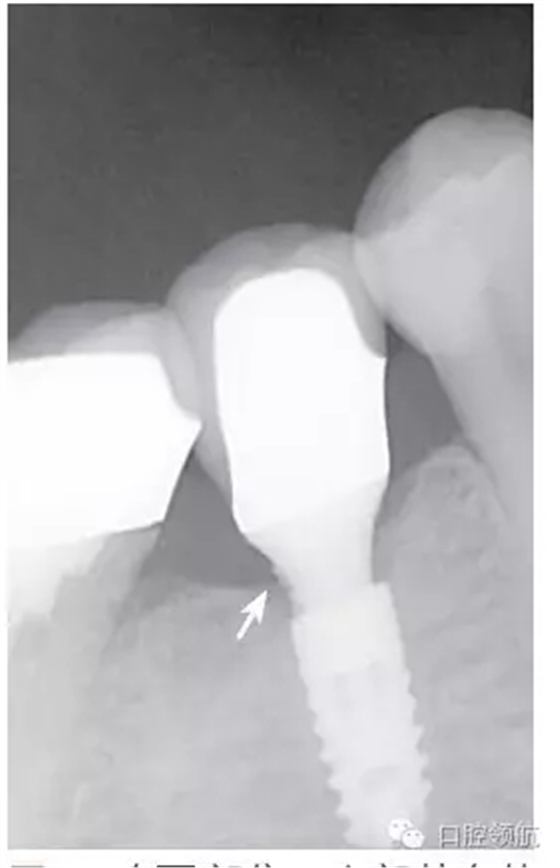

種植體的基臺(tái)與上部修復(fù)體的密合性,通過(guò)口腔X線片進(jìn)行檢查,確認(rèn)種植體周?chē)袣埩舻恼辰觿▓D2),使用探針等器械盡力清除剩余粘接劑,避免預(yù)后不良因素的產(chǎn)生。然后,通過(guò)X線片從投照的方向檢查確認(rèn)剩余的粘接劑,完全沒(méi)有殘留粘接劑的實(shí)際狀態(tài)(圖3)。

圖2 在(左下第五顆牙)部位,上部基臺(tái)的遠(yuǎn)中鄰面區(qū)域,看到了殘留的剩余粘接劑。